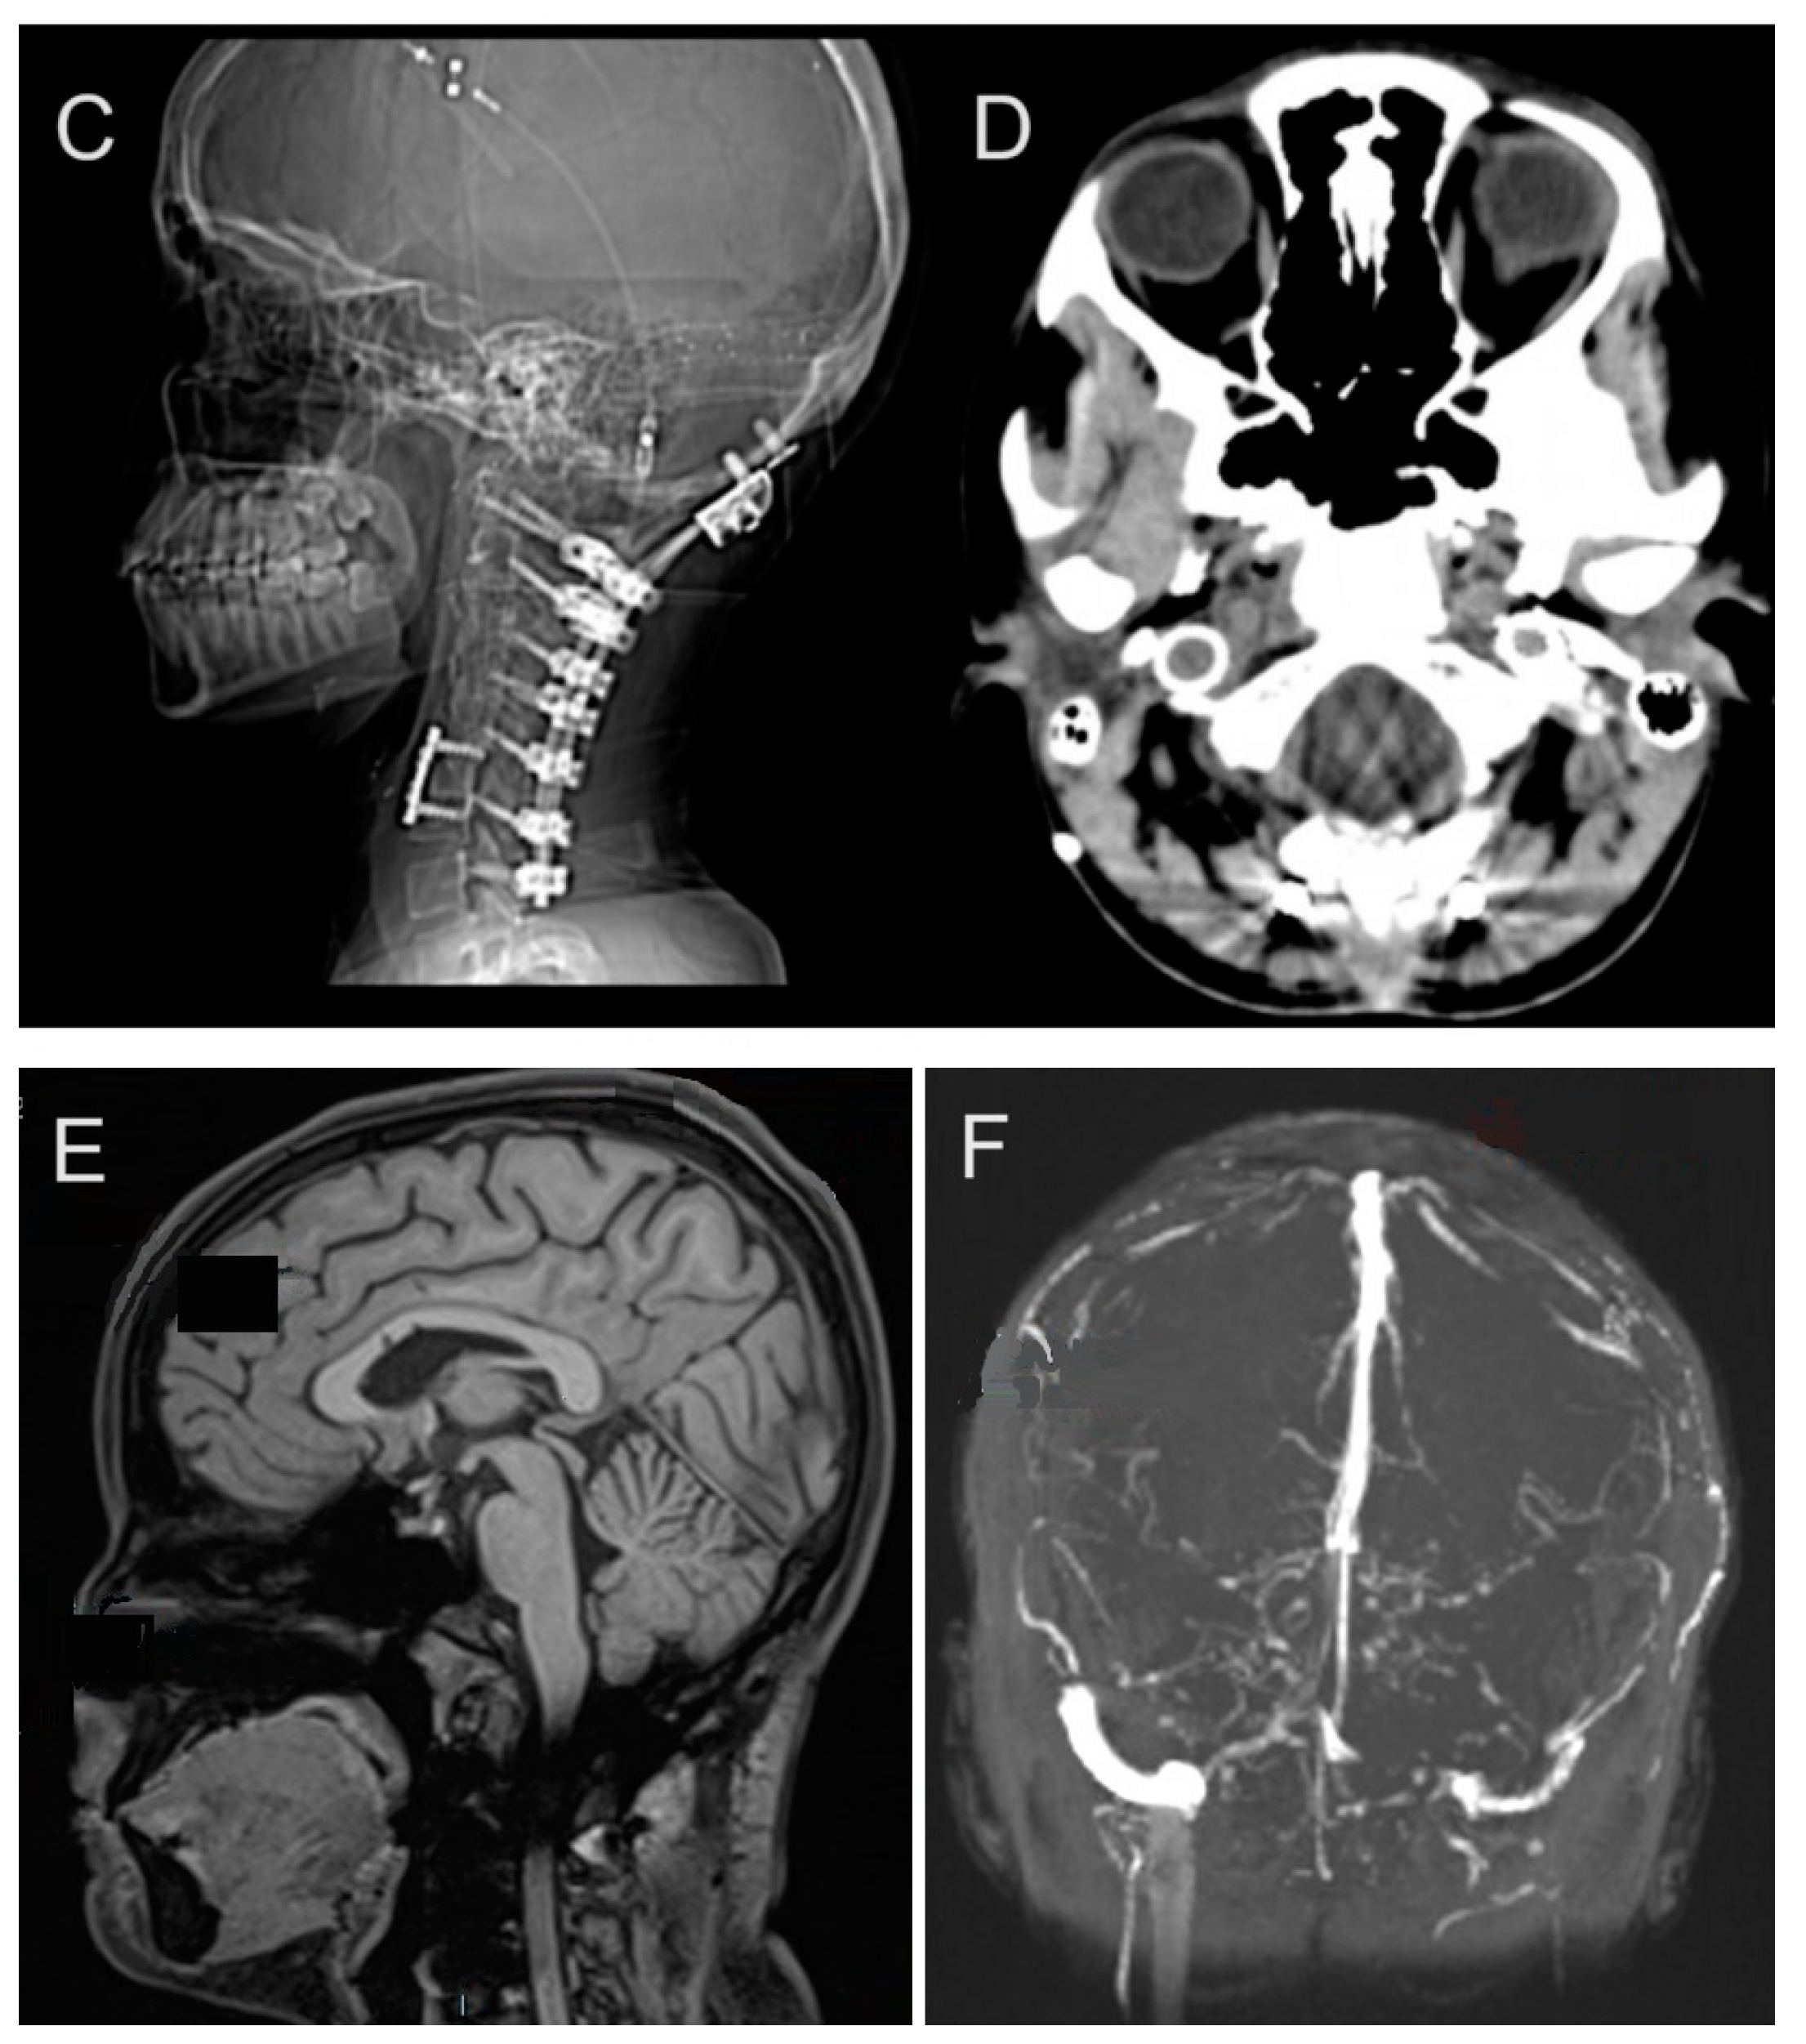

At age 12, she underwent tethered cord release surgery, which was complicated by multiple cerebrospinal fluid (CSF) leaks requiring blood patches and surgical revisions. This was followed by a series of spinal surgeries beginning with a skull-C2 fusion in 2013. Her vascular surgical history included multiple stenting procedures beginning in response to jugular vein stenosis, a condition linked to impaired blood flow from the brain with right internal jugular and transverse sinus stent placement. Despite these interventions, she continued to experience symptoms related to venous insufficiency and intracranial pressure. Idiopathic Intracranial Hypertension (IIH) management began at age 14 with initial ICP monitoring and lumbar shunt placement. This condition resulted in chronic headaches and required multiple surgical interventions. In 2014, she received a lumboperitoneal (LP) shunt placement, which was later removed in 2015 due to a crack in the tubing and followed by C2-C5 anterior cervical discectomy and fusion (ACDF) in 2015 (Figure 2A,B). This period also marked her initial diagnosis of pseudotumor cerebri. The following year, in 2016, she required left internal jugular stent for thrombus and obstruction, followed by superior sagittal sinus stent placement in 2017. These interventions were necessitated by recurring thrombosis and vascular complications associated with her hEDS. By 2019, further deterioration required additional surgeries including O-C7 fusion with removal of anterior hardware in June (Figure 2C,D) and C6/7 ACDF in December. Three separate repairs were required to address CSF leaks from the lumbar shunt removal site. The management continued to evolve, with additional procedures including sagittal sinus stent placement at age 17 and multiple VP shunt revisions.

Figure 2.

Longitudinal imaging findings in a patient with hEDS demonstrate progressive cervical spine instability and vascular complications. (A,B) A 2015 CT scan at age 15 showing post-surgical changes including occipital-C2 fusion and C2–C5 ACDF, with cervical lordosis straightening and C5–C6 anterolisthesis. Prior interventions included tethered cord release at age 12 and lumbar shunt placement at age 14 for IIH management. (C,D) CT in 2019 revealing expanded occipital-to-C7 fusion after hardware removal, necessitated by progressive cervical instability. (E) Brain MRI in 2016 demonstrates normal intracranial findings without restricted diffusion, hemorrhage, or tonsillar ectopia. (F) A 2016 angiogram showing asymmetric jugular veins with right-sided dominance, post-jugular foramen stenosis, and diminished left-sided flow.

The spinal interventions progressed in complexity, culminating in a repair from occipital to T5 at age 20. These procedures were necessitated by progressive cervical instability and neurological symptoms. By 2022, imaging revealed significant hardware-related complications, including screw lucency at C7 and adjacent pedicle fracture. She developed myofascial neck pain secondary to multiple fusion procedures, ultimately requiring surgical wound washout and debridement. In April 2022, she underwent ultrasound-guided aspiration of a posterior cervical fluid collection, removing 90cc of brownish/purulent fluid, followed by surgical wound washout and debridement.